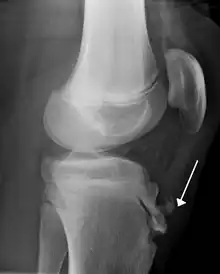

Examen radiologic

Examen radiologic al genunchiului se face în mod obligatoriu bilateral și numai din profil.

În mod normal, înainte de 10 ani, nu există o osificare a punctelor osoase reprezentând această tuberozitate. În cazul maladiei Osgood-Schlatter, tuberozitatea tibială se recurbează "în trompă de tapir" sau "buză de tapir", este fragmentată sau prezintă zone de condensare și zone clare de osificare insuficientă.